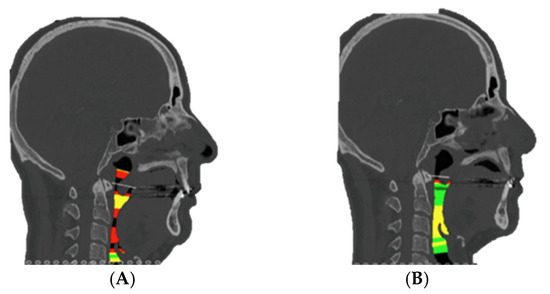

Additionally, stereolithographic (STL) models were printed at the 3D Printing Unit of the General University Hospital Gregorio Marañón to verify the position of the cutting guides, customized plates, and osteotomies during surgery (Figure 2).

An intraoral incision was designed in the upper vestibule, above the dental apices, extending from the right first molar to the left first molar. The mucoperiosteal flap was elevated to expose the maxilla. The bone-supported cutting guide was then positioned on the maxilla. Two cutting guides were designed, joined at the medial part, each with a tab for positioning on the piriform process. The cutting guide was designed to be fixed with 2.0 mm screws (Figure 3).

Figure 2. Step 2. Stereolithographic models showing final cutting guides and patient-specific titanium plates as part of the preoperative planning phase.